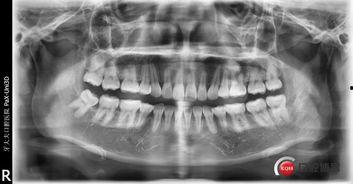

很多人可能会问,为什么成人还需要拔牙呢?其实,拔牙在成人中并不少见。以下是一些常见的成人拔牙原因:

智齿问题:智齿是第三磨牙,位于口腔最里面。由于智齿生长位置不理想,常常导致牙列拥挤、牙龈炎症等问题,不得不拔除。

牙齿损坏:由于意外伤害或长期磨损,一些牙齿可能已经无法修复,只能通过拔牙来解决问题。

牙齿排列不齐:为了矫正牙齿排列不齐,有时需要拔除一些牙齿,以便为其他牙齿腾出空间。

而这个视频,正是展示了成人拔牙的过程。通过这个视频,我们可以了解到拔牙并非想象中那么可怕,医生们会运用专业的技术和设备,确保手术顺利进行。